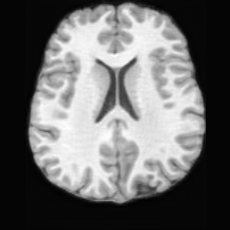

PathologicalSynthSR [18]Brain-ID [28]UNA [30]USBRefer to captionRefer to captionRefer to captionRefer to captionRefer to captionRefer to captionRefer to captionRefer to captionRefer to captionRefer to caption

Figure D.2: Comparison of pathology-to-healthy editing results on real stroke brain images with imaging artifacts from the ATLAS dataset [27]. The prominent elongated dark regions in the images correspond to artifacts.

Editing as Image Inpainting for Corrupted Scans. In clinical practice, various factors (e.g., patient motion, metallic implants, bias fields) can introduce artifacts and corruptions in the acquired MRI scans. As illustrated in Fig. D.2, such artifacts may occlude large brain regions, posing additional challenges for downstream image analysis. Experimental results indicate that other methods fail to handle such occluded regions, leaving the artifacts uncorrected in the edited images. In contrast, USB demonstrates strong inpainting capabilities, effectively reconstructing the lesioned areas while simultaneously restoring regions affected by imaging artifacts. This highlights USB’s robustness in editing real pathological scans even under challenging conditions, further validating its ability to generalize from pseudo-synthetic pathological training data to real clinical images.